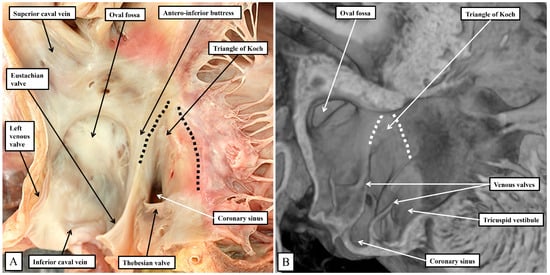

Removing the parietal walls of the right-sided chambers provides an en-face view of the septal atrioventricular junctions, and the septal surfaces of the morphologically right atrium and right ventricle (Figure 1A). A view of an episcopic dataset from a neonatal mouse prepared in a comparable fashion shows the similarities when the murine heart is positioned so as to parallel the human heart as viewed in an attitudinally appropriate fashion (Figure 1B).

As is shown in the photographs, when viewed attitudinally, the features are comparable. There are, however, subtle differences which impact on the location of the components of the atrioventricular conduction axis. Perhaps the most significant difference is the presence of a persistent left superior caval vein in the murine heart. This channel opens inferiorly into the vestibular region of the right atrium through an enlarged orifice of the coronary sinus (Figure 1B). In the human heart, the coronary sinus opens much more superiorly within the cavity of the right atrium (Figure 1A). The superior and inferior caval veins enter the systemic venous sinus in a comparable fashion in both species, but the opening of the venous sinus to the morphological right atrium is more dorsal in the murine heart (Figure 1B). The junction between the venous sinus and the remainder of the atrium is then much more obvious in the murine heart since the venous valves are much better preserved, with obvious right and left venous valves coming together at a superior commissure attached within the atrial appendage by the prominent pectinate muscle known as the septum spurium (Figure 1B). In the human heart, it is usually only parts of the right venous valve that persist. These remnants are the Eustachian valve, which partially guards the entrance of the inferior caval vein, and the Thebesian valve, which guards the opening of the coronary sinus (Figure 1A). The two valves come together at the area of the atrial wall separating the orifice of the coronary sinus from the oval fossa. Usually described as the sinus septum, the area is a fold between the walls of the inferior caval vein and the coronary sinus. The area of union between the valves then continues as a tendinous structure that runs within the antero-inferior buttress of the oval fossa. As we will describe, this fibrous entity, known as the tendon of Todaro, forms a boundary of the triangle of Koch, itself providing a landmark to the site of the atrial components of the conduction axis. The situation is more obvious in the murine heart since venous valves marking both the right and left borders of the systemic venous sinus remain subsequent to birth (Figure 1B). In the human heart, nonetheless, with careful examination, it is sometimes possible to recognize small remnants of the left venous valve plastered onto the septal surface of the oval fossa and its surrounds. In the murine heart, the right and left venous valves form a tunnel that directs the flow from the inferior caval vein toward the oval fossa. The superior extension of both valves into the area between the coronary sinus and the oval fossa is also much more marked, with a triangular area such as described initially by Koch also to be found in the mouse heart (see below). There are also subtle differences in the arrangement of the oval fossa between the species. In the human heart, the superior rim of the fossa is an obvious infolding between the attachments of the superior caval vein to the right atrium, and the right pulmonary veins to the left atrium. This arrangement is not found in the murine heart since the pulmonary veins open to the morphologically left atrium through a common orifice located inferiorly rather than superiorly, with a fold present in the dorsal wall, rather than superiorly as found in the human heart. The flap valve of the oval fossa in the murine heart closes against the roof of the atrium, such that the dorsal fold is not obvious (Figure 2A), rather than directly against the superior interatrial fold as is the case in the human heart.

It is the septal surfaces of the right atrium, however, that provide the key landmarks to the location of the atrial components of the atrioventricular conduction axis. And here again, the arrangements between the species are similar, albeit with subtle differences. These differences again reflect, for the larger part, the presence in the murine heart, of the persistent left superior caval vein, and the enlarged orifice of the coronary sinus. This means, as already discussed, that the orifice of the coronary sinus, guarded by the Thebesian valve, is positioned more superiorly in the human heart when compared with the arrangement seen in the murine heart. In both species, nonetheless, it remains possible to recognize how the Eustachian and Thebesian valves come together, extending to run as the tendon of Todaro within the atrial walls interposing between the orifice of the coronary sinus and the oval fossa. The arrangement is more obvious in the murine heart since the orifice of the coronary sinus itself extends to occupy the inferior component of the chamber when viewed in an attitudinally appropriate arrangement for the human heart (Figure 5).

In both species, therefore, it is possible to recognize the important triangle as initially described by Koch [18]. The apex of the triangle, in the human heart, is adjacent to the infero-septal recess of the left ventricular outflow tract, albeit the spaces are separated by the atrioventricular septal structures (Figure 4B). In the murine heart, in contrast, the aortic root is located more superiorly when viewed in an attitudinally appropriate fashion, reflecting the lack of wedging when compared to the human heart (Figure 3). The greater inferior extent of the orifice of the coronary sinus in the murine heart (Figure 5B) then produces a major difference in the structure of the cavo-tricuspid isthmus. In the human heart, the isthmus incorporates an extensive sub-Thebesian sinus (Figure 5A). In the murine heart, again when considered attitudinally, the vestibular sinus is anterior, rather than inferior, when assessed relative to the Thebesian valve (Figure 5B). All of these subtle changes between the human and murine hearts in terms of the gross anatomy are then significant when set against the location of the atrioventricular conduction axis in the two species.

Figure 1. (A) shows the features of the morphologically right atrium and ventricle of the human heart, having removed their parietal walls, with the heart shown in an attitudinally appropriate position. (B) shows an image from an episcopic dataset from a neonatal mouse heart sectioned to parallel the arrangement as seen in (A). The features are basically the same, although, as explained in the text, there are subtle differences that impinge on the arrangement of the atrioventricular conduction axis.

Figure 5. The images show the septal surface of the right atrioventricular junction in the human heart (A) compared to the murine heart (B). The dashed lines in panels A and B delimit the Koch triangle. In both species, the extension of the fold of the venous valve between the orifice of the coronary sinus and the oval fossa produces the border of the triangle named for Koch. As we will describe, in both species, the atrioventricular node lies beneath the septal vestibule at the apex of the triangle formed with the hinge of the septal leaflet of the tricuspid valve.